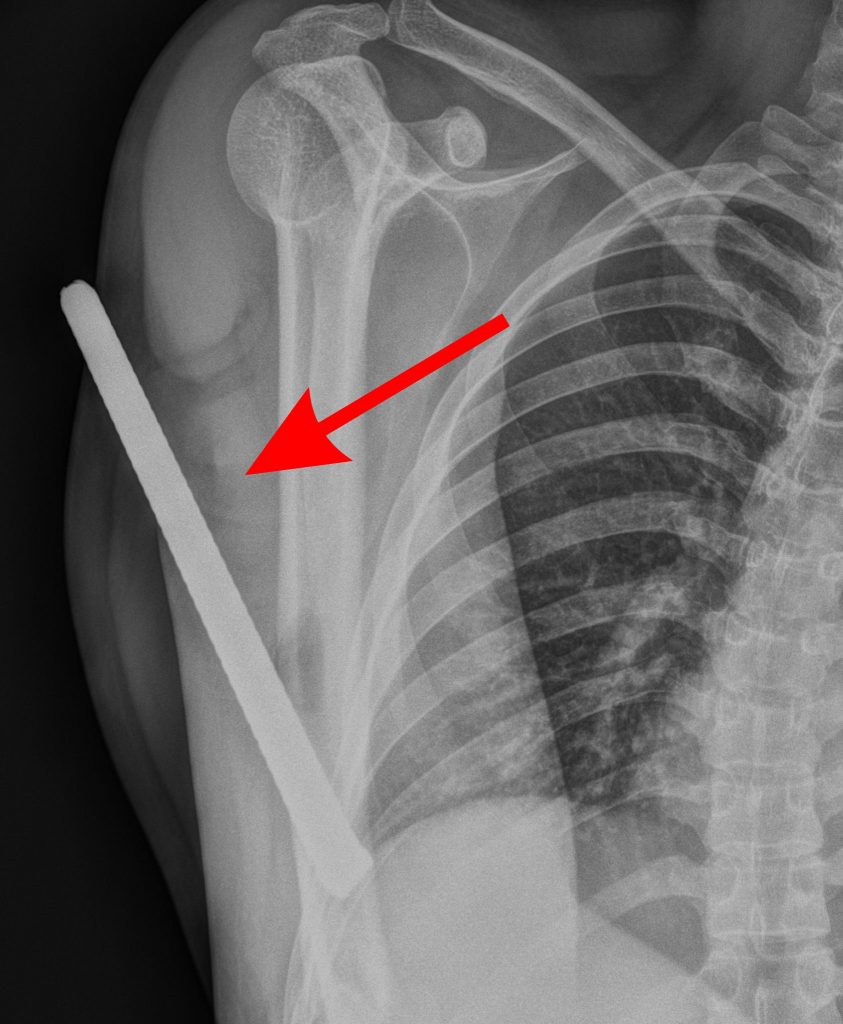

Tại Khoa Cấp cứu, các bác sĩ nhanh chóng thăm khám và ghi nhận dị vật đâm xuyên từ mặt sau đầu trên cánh tay phải, không thấy đầu còn lại của dị vật.

Hình ảnh X-Quang

Trong quá trình mổ, ê-kíp ghi nhận thanh sắt đâm xuyên cánh tay từ 1/3 trên xương cánh tay xuống vùng đầu dưới xương cánh tay phải, gây đứt một phần gân cơ nhị đầu và đầu dài gân cơ tam đầu cánh tay, rách màng xương cánh tay và lẫn nhiều đất cát trong vết thương.